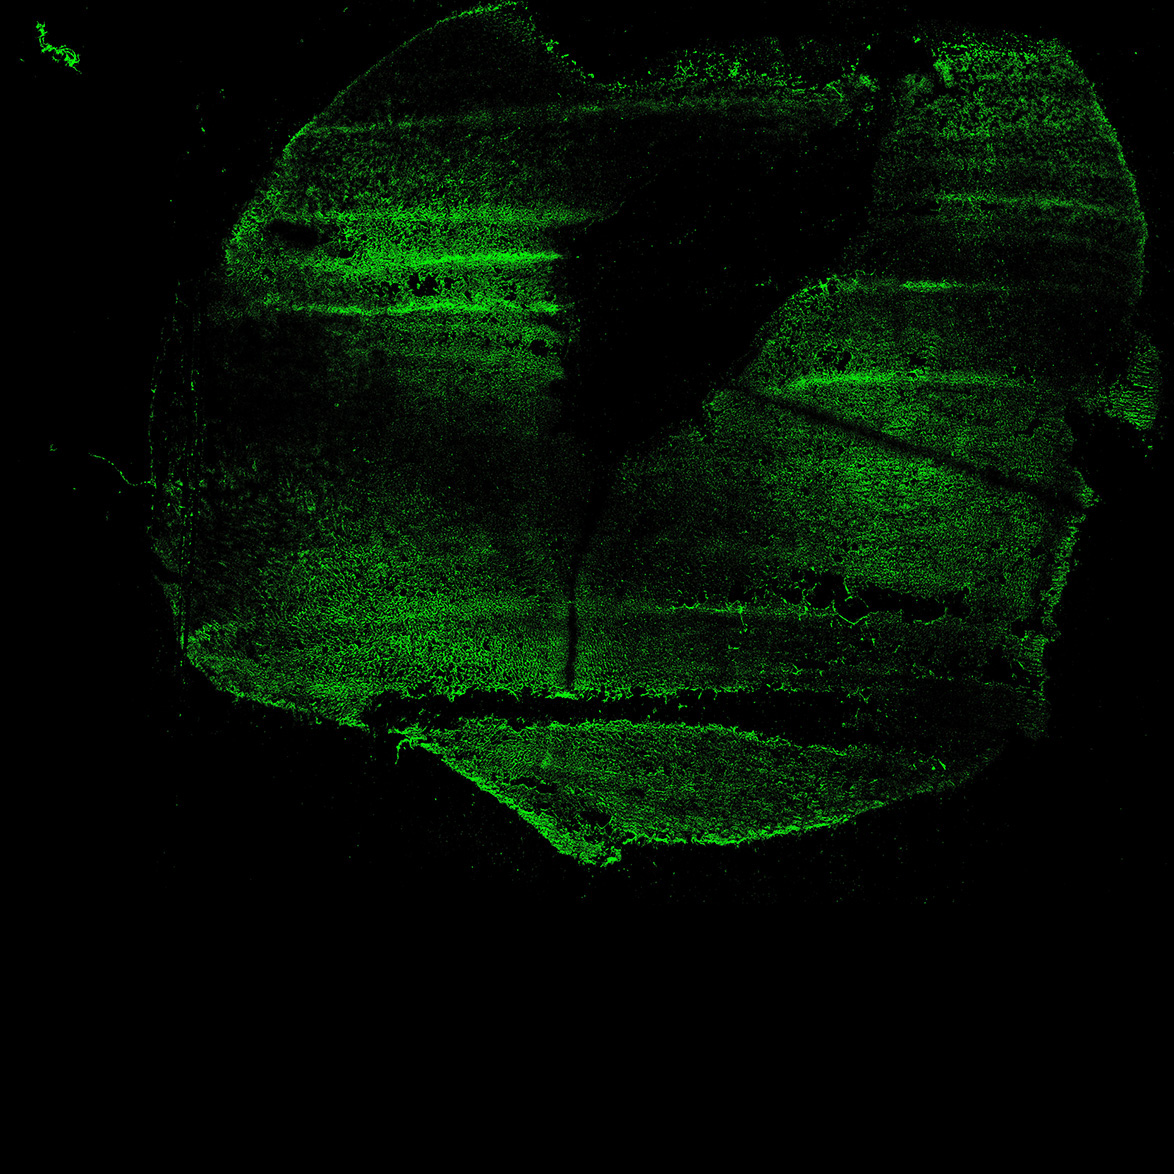

An anatomical analysis of the developing human midbrain from 6 post-conceptional weeks (PCW) to 22 PCW reveals increased tissue complexity, characterized by the emergence of dopaminergic nuclei, as highlighted by immunofluorescence analysis for tyrosine hydroxylase (TH).

17PCW

DAPI

17PCW human midbrain

MAP2

TH

Merged

11PCW human midbrain